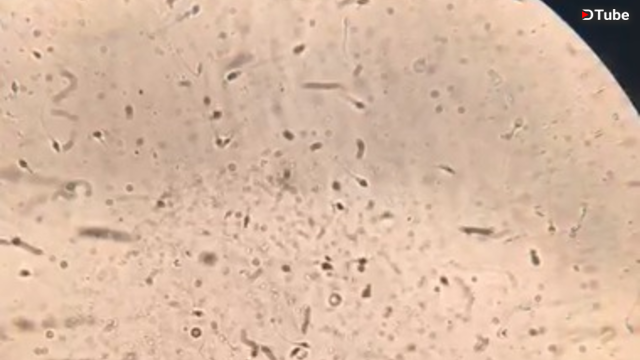

La tarde de hoy en la universidad, como parte de la práctica de "MEIOSIS" me tocó analizar en el microscopío óptico a los espermatozoides, y me pareció interesante. Asi que decidi compartir con ustedes un poco de esto.

¿Sabias que los hombres saludables producen cerca de 70 a 150 millones de espermas al día?